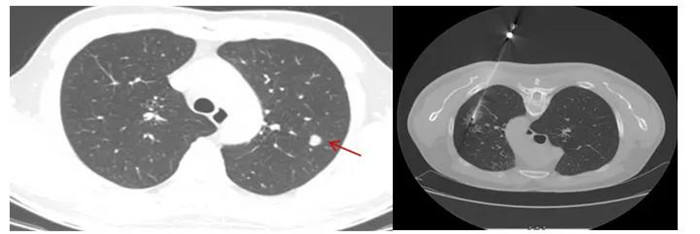

CT引導(dǎo)下肺穿刺活檢,8毫米肺結(jié)節(jié)排除肺癌可能

“通過(guò)CT掃描測(cè)量,確定穿刺進(jìn)針點(diǎn)、方向、距離,使用肺穿刺針經(jīng)胸壁穿刺到肺結(jié)節(jié)部位,進(jìn)行3~4次切割取材,獲取組織送檢驗(yàn)及病理切片?!睉c幸的是,穿刺結(jié)果顯示,黃先生的肺結(jié)節(jié)為:肺隱球菌病。

CT定位下經(jīng)皮肺穿刺活檢

行CT引導(dǎo)下經(jīng)皮肺穿刺活檢術(shù)前,患者需要排除近期服用抗凝藥物、自身凝血障礙等禁忌癥,術(shù)前完善CT增強(qiáng)掃描,以顯示肺結(jié)節(jié)與周圍血管分布的關(guān)系,明確穿刺時(shí)的位置選取,最大程度避免傷及血管,減少出血風(fēng)險(xiǎn)。